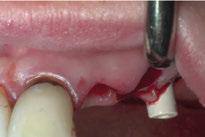

Para ilustrar el proceso, presentamos el caso de una mujer joven diagnosticada de carcinoma adenoide quístico en la región posterior del hemipaladar izquierdo (Figuras 1 y 2). El procedimiento quirúrgico realizado fue una

maxilectomía parcial que incluyó las piezas 24-26 y desde el reborde alveolar hasta la base del cráneo (Figuras 3 y 4). En este caso, la órbita y el globo ocular pudieron ser preservados. La reconstrucción inmediata se realizó mediante un colgajo de músculo temporal homolateral (Figura 5) y el defecto de la fosa temporal fue cubierto mediante una malla de titanio. Posteriormente, la paciente recibió radioterapia (Figuras 6 y 7). 2 años más tarde se diseñó un IS con anclaje en el arbotante nasomaxilar, zona subnasal izquierda

Figura 1. Imagen preoperatoria de la paciente.

Figura 2. Carcinoma adenoide quístico en región posterior del hemimaxilar izquierdo.

Figura 3. Maxilectomía parcial.

Figura 4. Defecto maxilar tras resección del tumor.